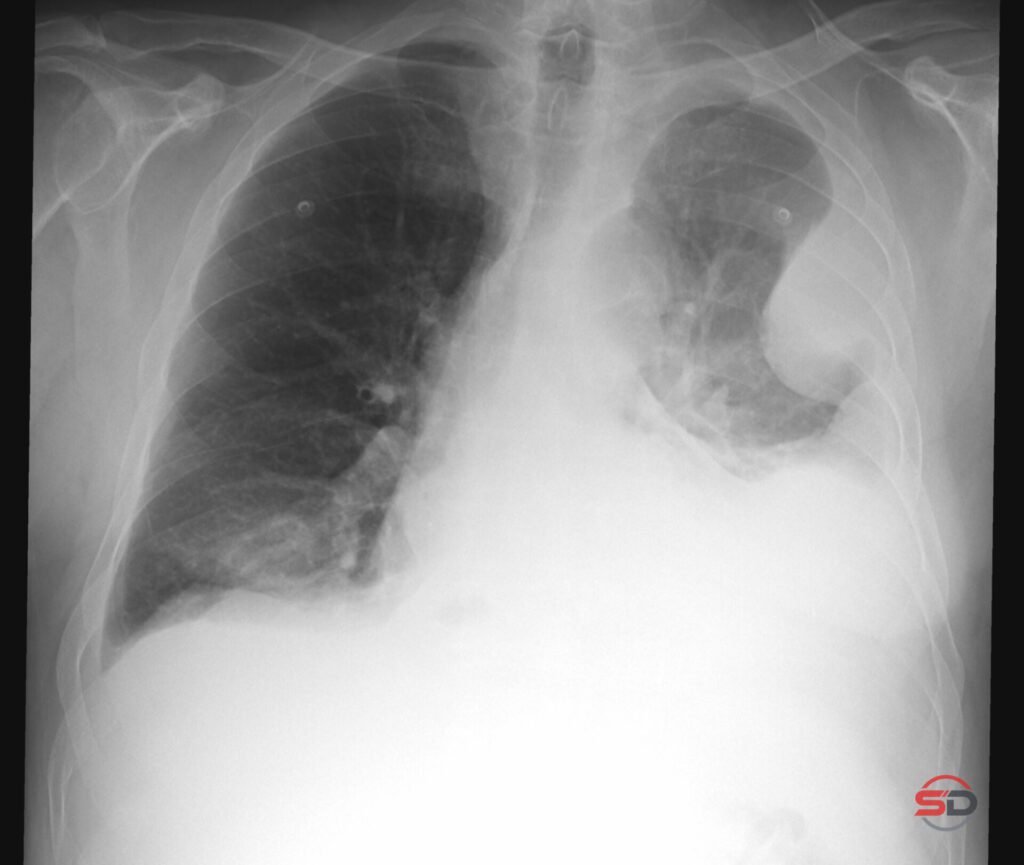

Pleuraerguss im Thoraxröntgen

Pleuraerguss im Thoraxröntgen Der Pleuraerguss gehört zu den häufigsten Befunden in der konventionellen Thoraxdiagnostik. Im klinischen Alltag ist das Thoraxröntgen […]